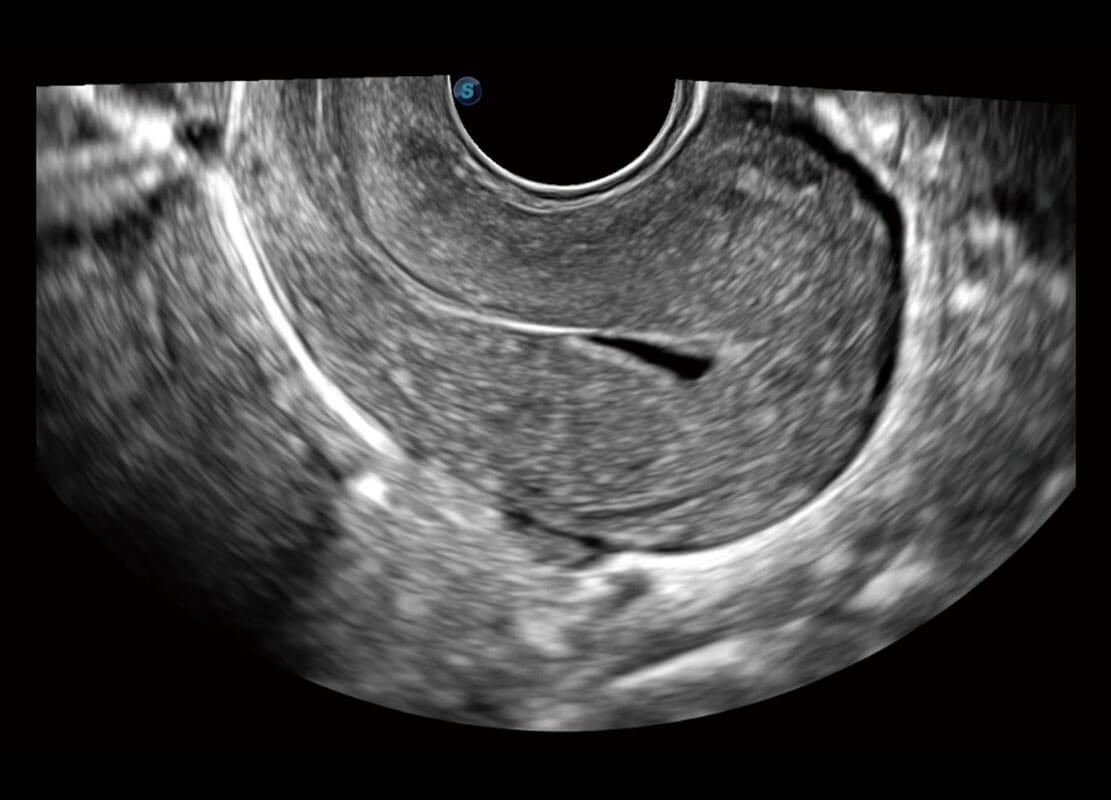

生殖健康

P60优异的图像质量搭载专科探头,在妇科基础疾病的诊断、卵泡生长的监测、输卵管通畅情况的判别等方面为您提供生殖应用方案。

• 腔内妇科-宫腔分离